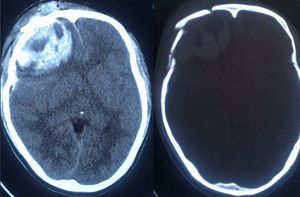

Intracranial haemorhagic with depressed skull fracture